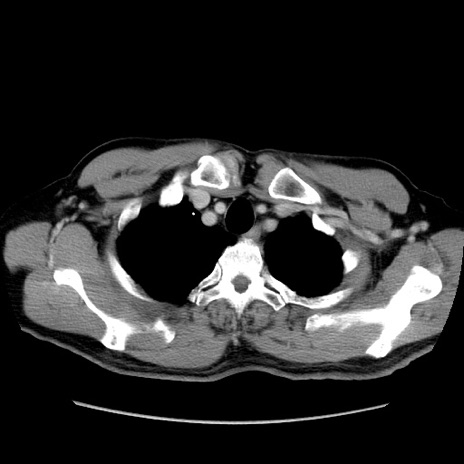

症例34(横断像)

【症例】60歳代 男性

【主訴】右鼠径部膨隆

【現病歴】1年程前より右鼠径部膨隆あり。自己にて還納可能だったため放置していた。3時間前より右鼠径部の脱出を認め、還納困難となり受診。

【既往歴】高血圧

【身体所見】右鼠径部に小児頭大の膨隆あり。弾性硬であり、用手還納は困難。左鼠径部にも膨隆を認める。脱出はなし。

【データ】WBC 15500、CRP 測定なし